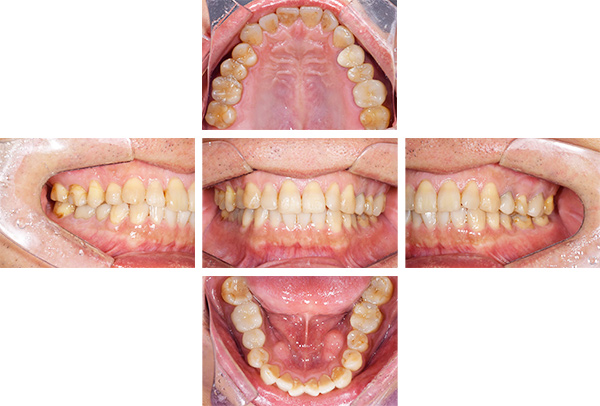

インレー症例

治療前

治療後

治療期間 4回(1ヶ月)

費用 セラミックインレー8本

合計:440,000円

治療リスク・副作用 ・詰め物、被せ物をする時は自分の歯を削ることになります

・歯ぎしり・食いしばりが強い方は、セラミックが割れてしまうことがあります。